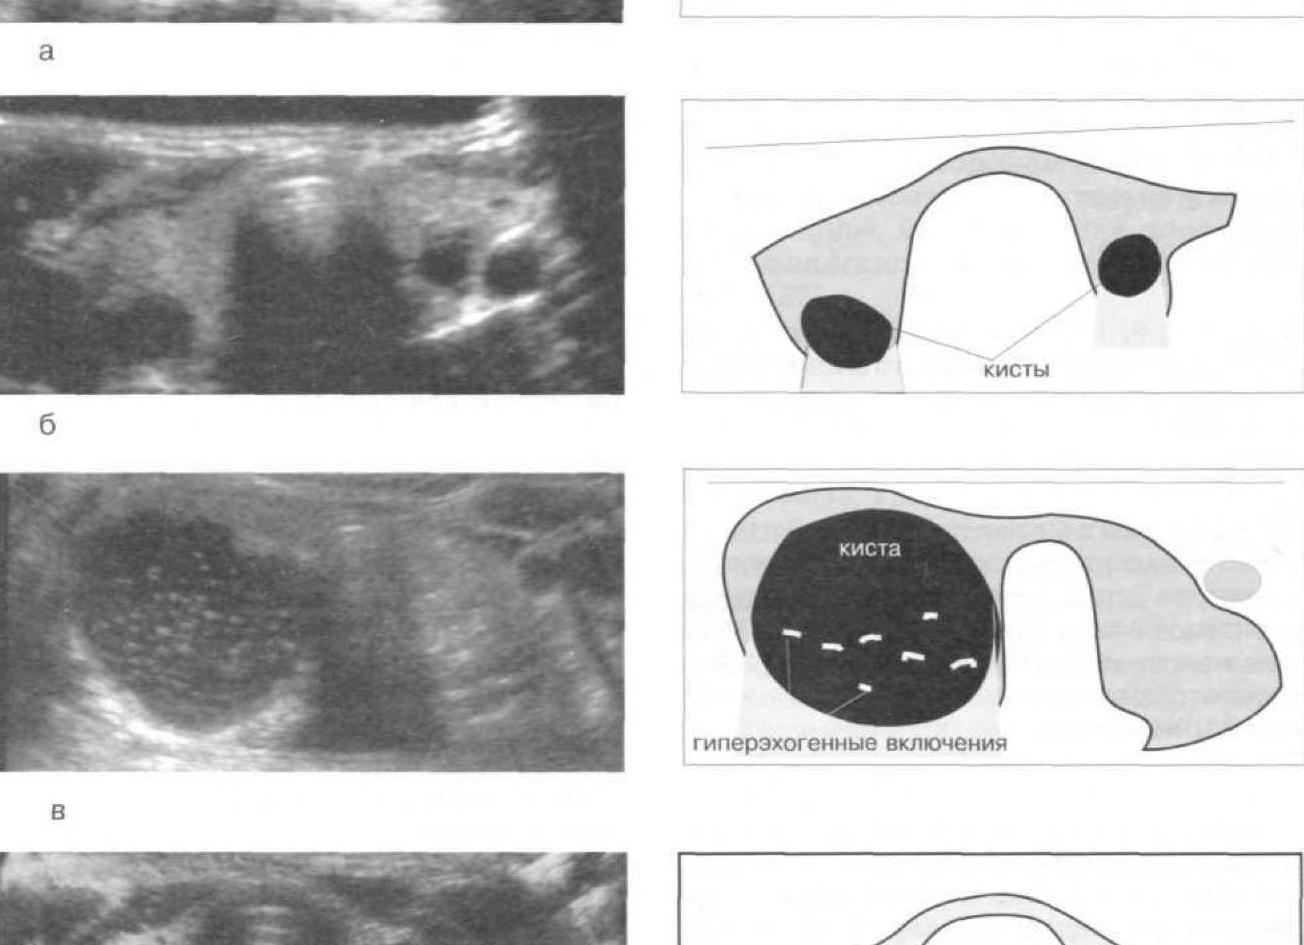

Это однокамерные, очень редко двухкамерные, чисто эхонегативные образования с тонкими гладкими стенками, с ровными четкими контурами, размеры которых варьируют от 2 до 11 см и более. Позади них почти всегда присутствует эффект акустического усиления. Чаще встречаются у женщин с воспалительными заболеваниями придатков и у больных с миомами, однако эта взаимосвязь непостоянна.

Паровариальные кисты

Это однокамерные жидкостные образования, чаще овально-удлиненной формы, эхографически ничем не отличающиеся от фолликулярных кист. Исходят они из надъяичникового придатка и располагаются между широкой связкой сбоку от матки. Размеры значительно варьируют — от малых до значительных (гигантские кисты). В наших наблюдениях у 57 (0,2%) женщин были выявлены кисты диаметром более 200 мм, из них у 9 масса кист достигала 9-22 кг, причем у 5 больных кисты занимали всю брюшную полость, больные находились на диспансерном учете (цирроз печени в асцитической стадии).

Единственный эхографический признак, который позволяет в какой-то степени дифференцировать паровариальную кисту от фолликула, — это выявление яичника как отдельной анатомической структуры. Однако эхолокация структуры яичника возможна лишь при наличии небольших кист. Паровариальные кисты не реагируют на противовоспалительную и гормональную терапию.

Кисты желтого тела

Имеют схожую эхографическую картину с фолликулярной и паровариальной кистой и обычно локализуются позади матки, имеют округлую или овальную форму, размеры не превышают 4-5 см, внутренняя структура иногда мелкодисперсна.

Текалютеиновые кисты

Это двухстороннее эхонегативное образование овальной формы с довольно четкими контурами, размеры не более 6 см в диаметре, их невозможно отличить от кистом.